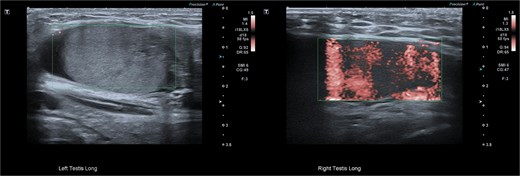

Although testicular torsion is a clinical diagnosis, we felt that the complexity of this case warranted ultrasound, which was immediately available and demonstrated no vascular flow to the left testis and normal perfusion to the right (Fig. 2). Given these findings and suspicion of torsion, emergency exploration was undertaken at our rural facility under paediatric surgical advice obtained from a tertiary centre.

Pre-operative ultrasonographic image demonstrating left and right intracanalicular testis. The left testis has absent colour Doppler flow and heterogeneous echotexture concerning for compromised perfusion.